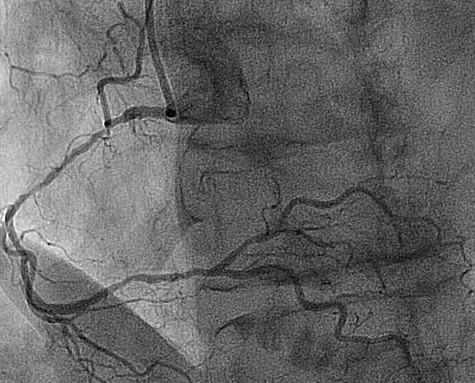

Left dominance: the posterior descending artery is a branch of the left coronary artery (segment 15). Co-dominance does not exist as an option in the SYNTAX score.